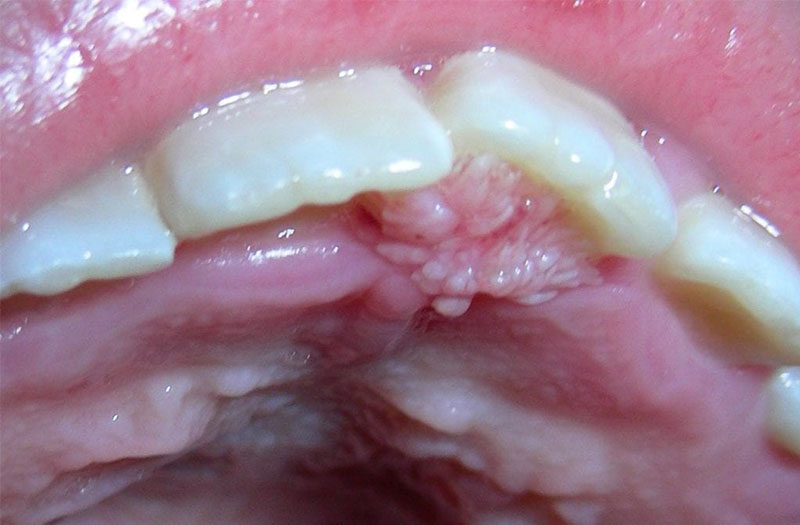

Sùi mào gà (còn gọi là bệnh mồng gà, mụn cóc sinh dục) là bệnh lây truyền qua đường tình dục, gây ra bởi virus Human Papilloma Virus (HPV). Bệnh thường gây ra các mô sùi có hình dạng giống như súp lơ hay mào gà. Chúng có thể xuất hiện trên bề mặt da hoặc màng nhầy xung quanh vùng sinh dục, hậu môn và thậm chí cả miệng. Mặc dù không nguy hiểm đến tính mạng nhưng sùi mào gà có thể gây đau, ngứa, chảy máu, ảnh hưởng đến sự tự tin cũng như các mối quan hệ với bạn đời/bạn tình.

Bệnh sùi mào gà là bệnh gây u nhú, mụn có hình mào gà